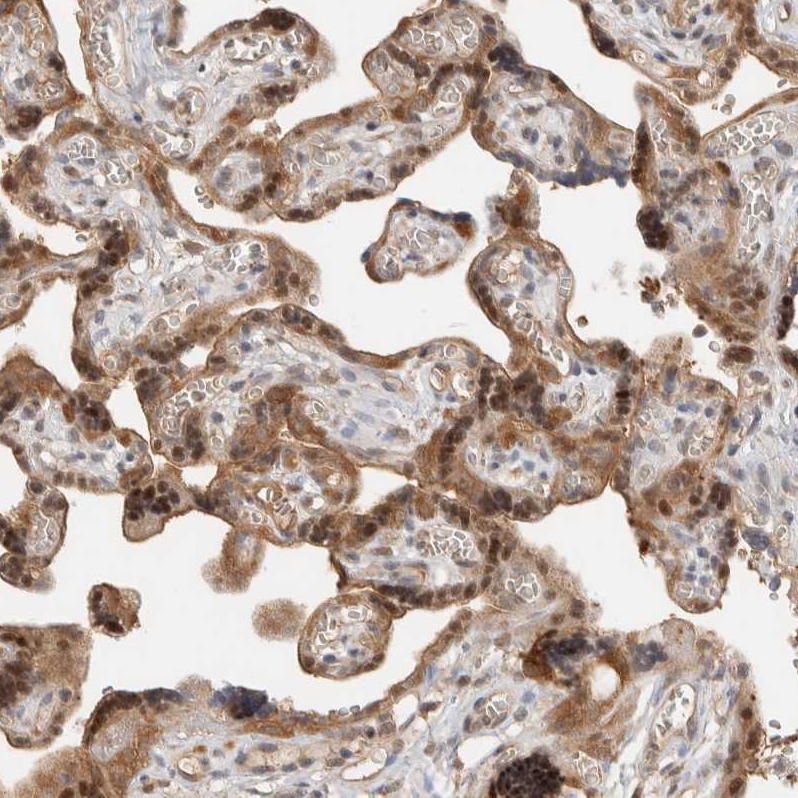

Immunohistochemical staining of human placenta shows moderate nuclear and cytoplasmic positivity in trophoblastic cells.